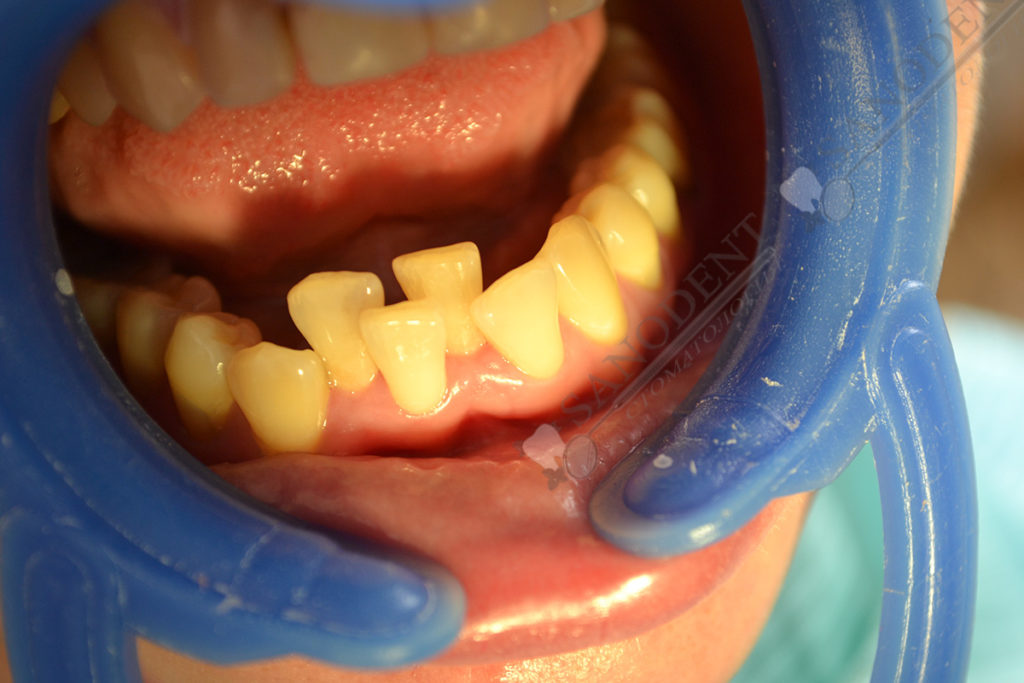

Установка керамических виниров и коронок на зубы с коррекцией положения зубов на нижней челюсти. Фото до и после, (E-max протезирование винирами и коронками)

- нарушение прикуса

- проблемы прикуса на нижней челюсти